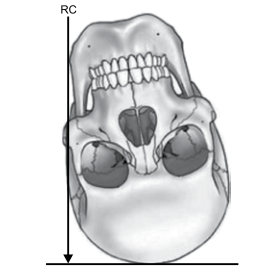

Na figura, a incidência representada é a

Provas

Sobre a anatomia e técnicas radiológicas do crânio, assinale a alternativa correta.